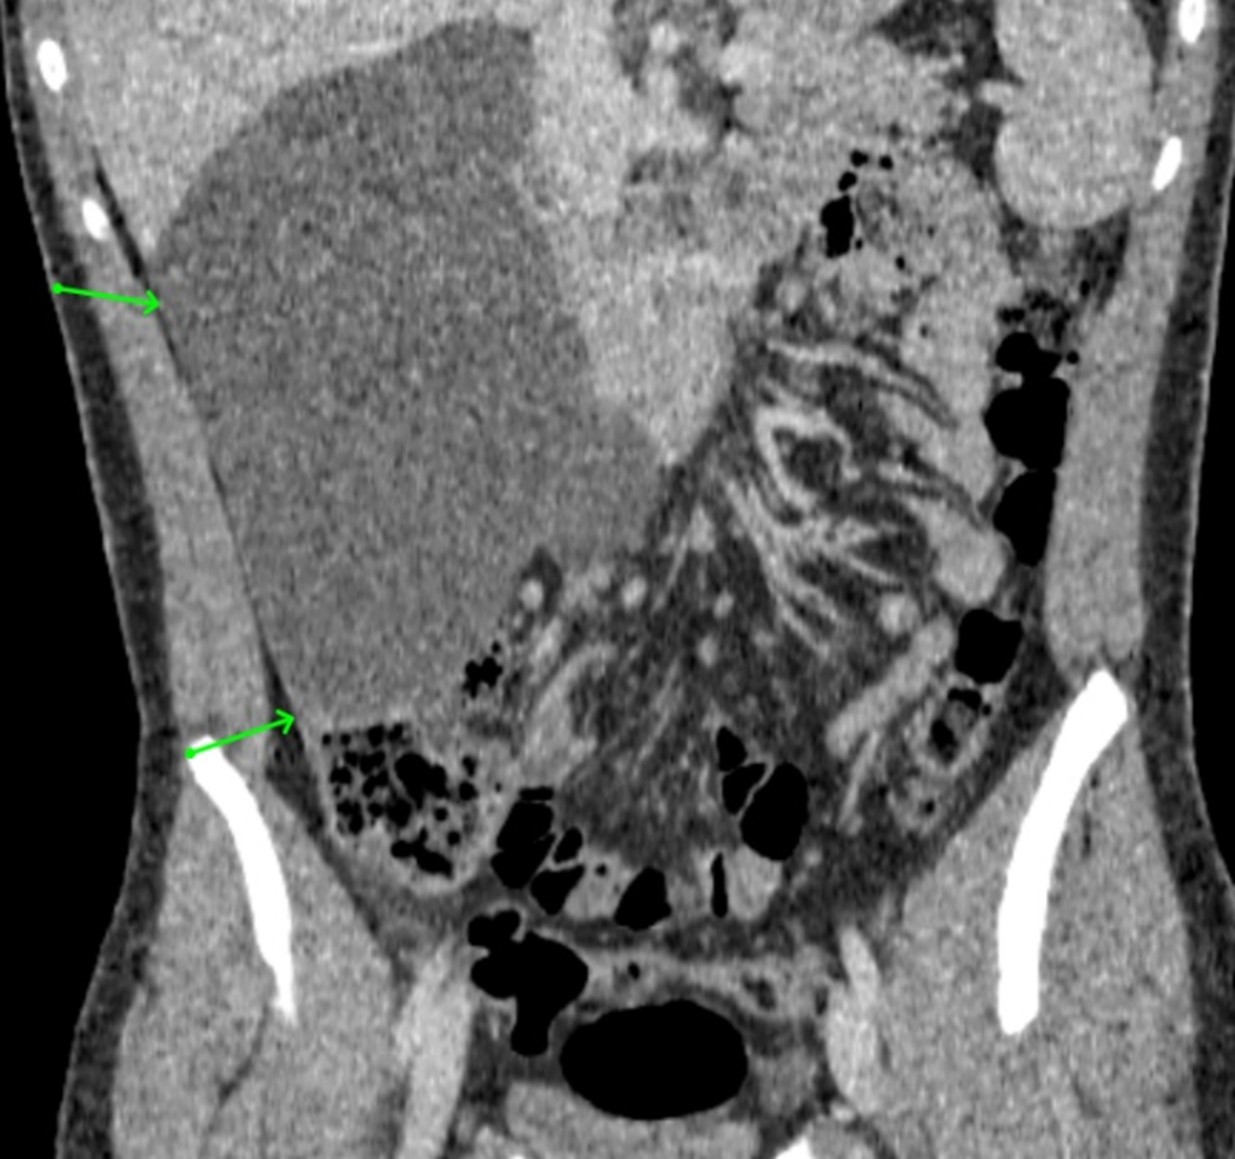

Xanthogranulomatous Pyelonephritis: An Uncommon Form of Pyelonephritis Highlighted in a Case Report

Danielle Malavazi Oliveira; Bárbara Sthefany de Paula Lacerda; Matheus Compart Hemerly, Maria Isabel Lima dos Santos, Weverton Machado Luchi

Malignant Rhabdoid Tumor of the Kidney in an 11-Month-Old Child: Case Report and Literature Review

Laura Mendes Lopes, Fabricio Grenteski, Carlos Roberto Naufel Júnior , Guilherme Andrade Coelho, Guilherme Ferrarini Furlan, Nertan Tefilli, José Anderson Feitoza , Igor Luna Peixoto

Acute Obstructive Abdomen Due to Gallstone Ileus: Case Report and Literature Review

Fabricio Grenteski, Laura Mendes Lopes, Gabriel Rodrigo Cavalheiro, Gustavo Henrique Morcelli da Costa, Carlos Roberto Naufel Júnior, Guilherme de Andrade Coelho, Guilherme Ferrarini, Igor Luna Peixoto, José Anderson Feitoza